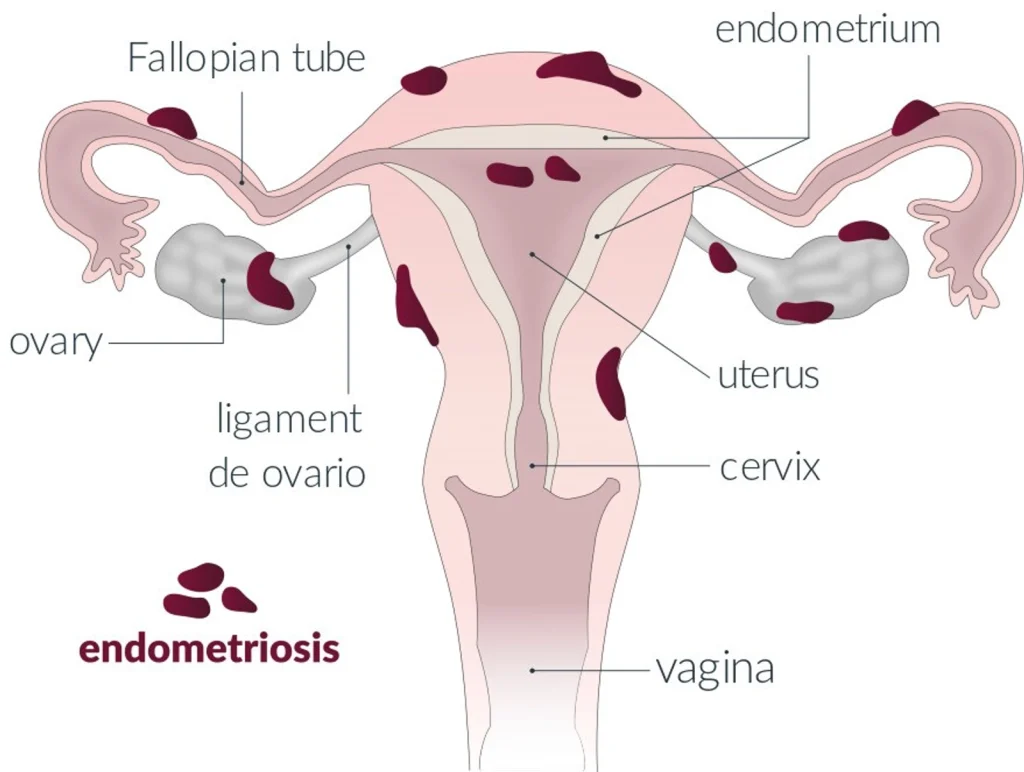

L’endométriose est une maladie qui touche 10 à 20 % des femmes dans le monde. Caractérisée par le développement d’un tissu semblable à l’endomètre en dehors de la cavité utérine, elle provoque de violentes douleurs aux personnes qui en souffrent, notamment pendant les règles, les rapports sexuels, et de nombreuses activités anodines du quotidien. Il a fallu attendre 160 ans depuis sa découverte avant que cette souffrance ne soit considérée, et n’entre dans les programmes des études de médecine en septembre 2020.

Les zones de migrations du tissu endométrial, qui tapisse normalement la cavité utérine, peuvent être nombreuses et plus ou moins étendues dans la cavité abdominale. Ces migrations provoquent des réactions inflammatoires chroniques très douloureuses, lesquelles impliquent des lésions internes. L’OMS définit 4 types de lésions. La première est qualifiée « d’endométriose superficielle », principalement localisée dans le péritoine pelvien. La deuxième, « l’endométriome » ou « kyste ovarien » est localisée dans les ovaires. Il y a ensuite « l’endométriose profonde », localisée dans le septum recto-vaginal, la vessie et le rectum. Enfin, dans de rares cas, l’endométriose peut migrer hors du bassin, jusque dans les poumons.

Il existe deux principaux types de symptômes. Tout d’abord, il s’agit de douleurs pelviennes, notamment pendant les règles qui sont souvent insupportables et abondantes. Les douleurs peuvent également survenir lors des rapports sexuels. L’endométriose peut également entraîner des dérèglement digestifs et des douleurs lors de l’émission des selles. Outre le facteur douleur, certaines personnes atteintes d’endométriose peuvent être concernées par des problèmes d’infertilité.